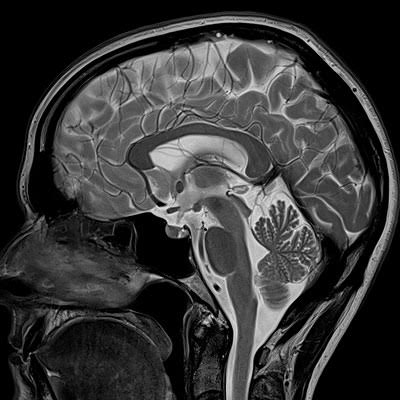

Our High-field MRI captures high-quality images. Our technicians who operate the scanner are certified in MRI and will stay in constant communication with you throughout your scan.

An MRI of the soft-tissue structures of the body—such as the heart, liver and many other organs - are more likely in some instances to identify and accurately characterize diseases than other imaging methods. This detail makes MRI an invaluable tool in early diagnosis and evaluation of many focal lesions and tumors.

MRI uses a powerful magnetic field, radio frequency pulses and a computer to produce detailed pictures of organs, soft tissues, bone and virtually all other internal body structures. The images can then be examined on a computer monitor, transmitted electronically, printed or copied to a CD. MRI does not use ionizing radiation (x-rays).

Detailed MR images allow physicians to evaluate various parts of the body and determine the presence of certain diseases. - How should I prepare for the procedure?